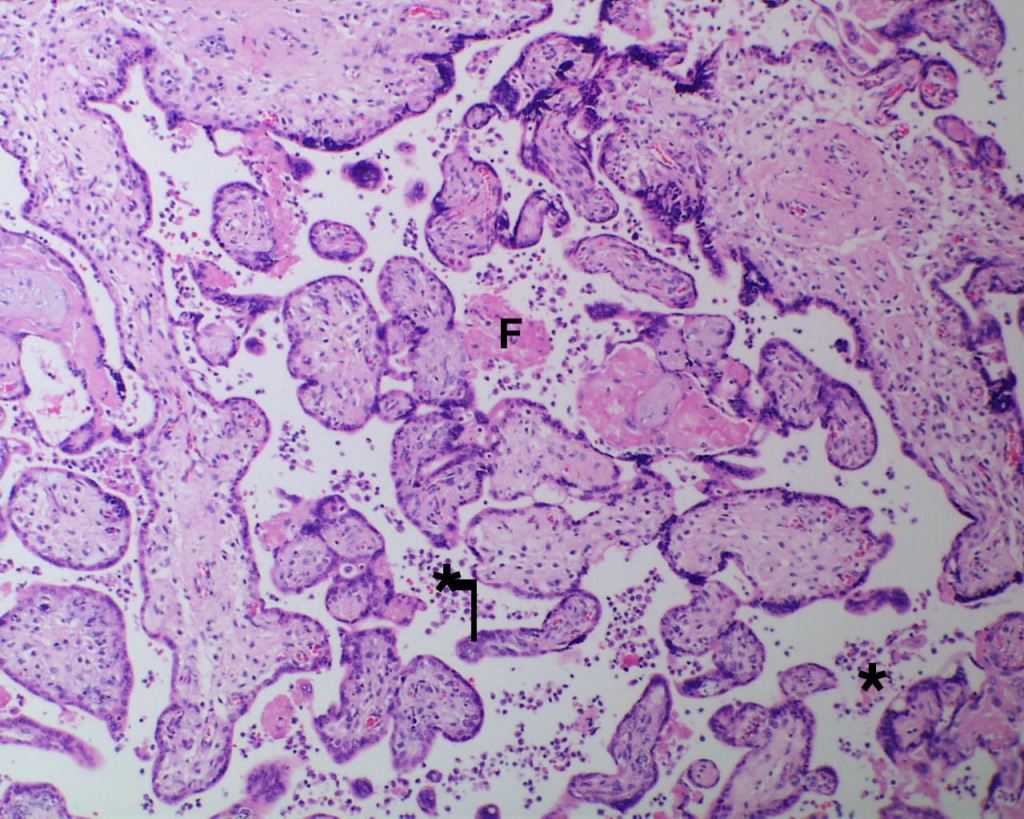

High Grade (massive) CHIV

Low Grade CHIV (5-50% of the intervillous space occupied by monocytes)

There is a focus of intervillous fibrinoid with no definite cytotrophoblast that is not re-covered with syncytium suggestive of recent syncytial injury (F). (10x, H&E)